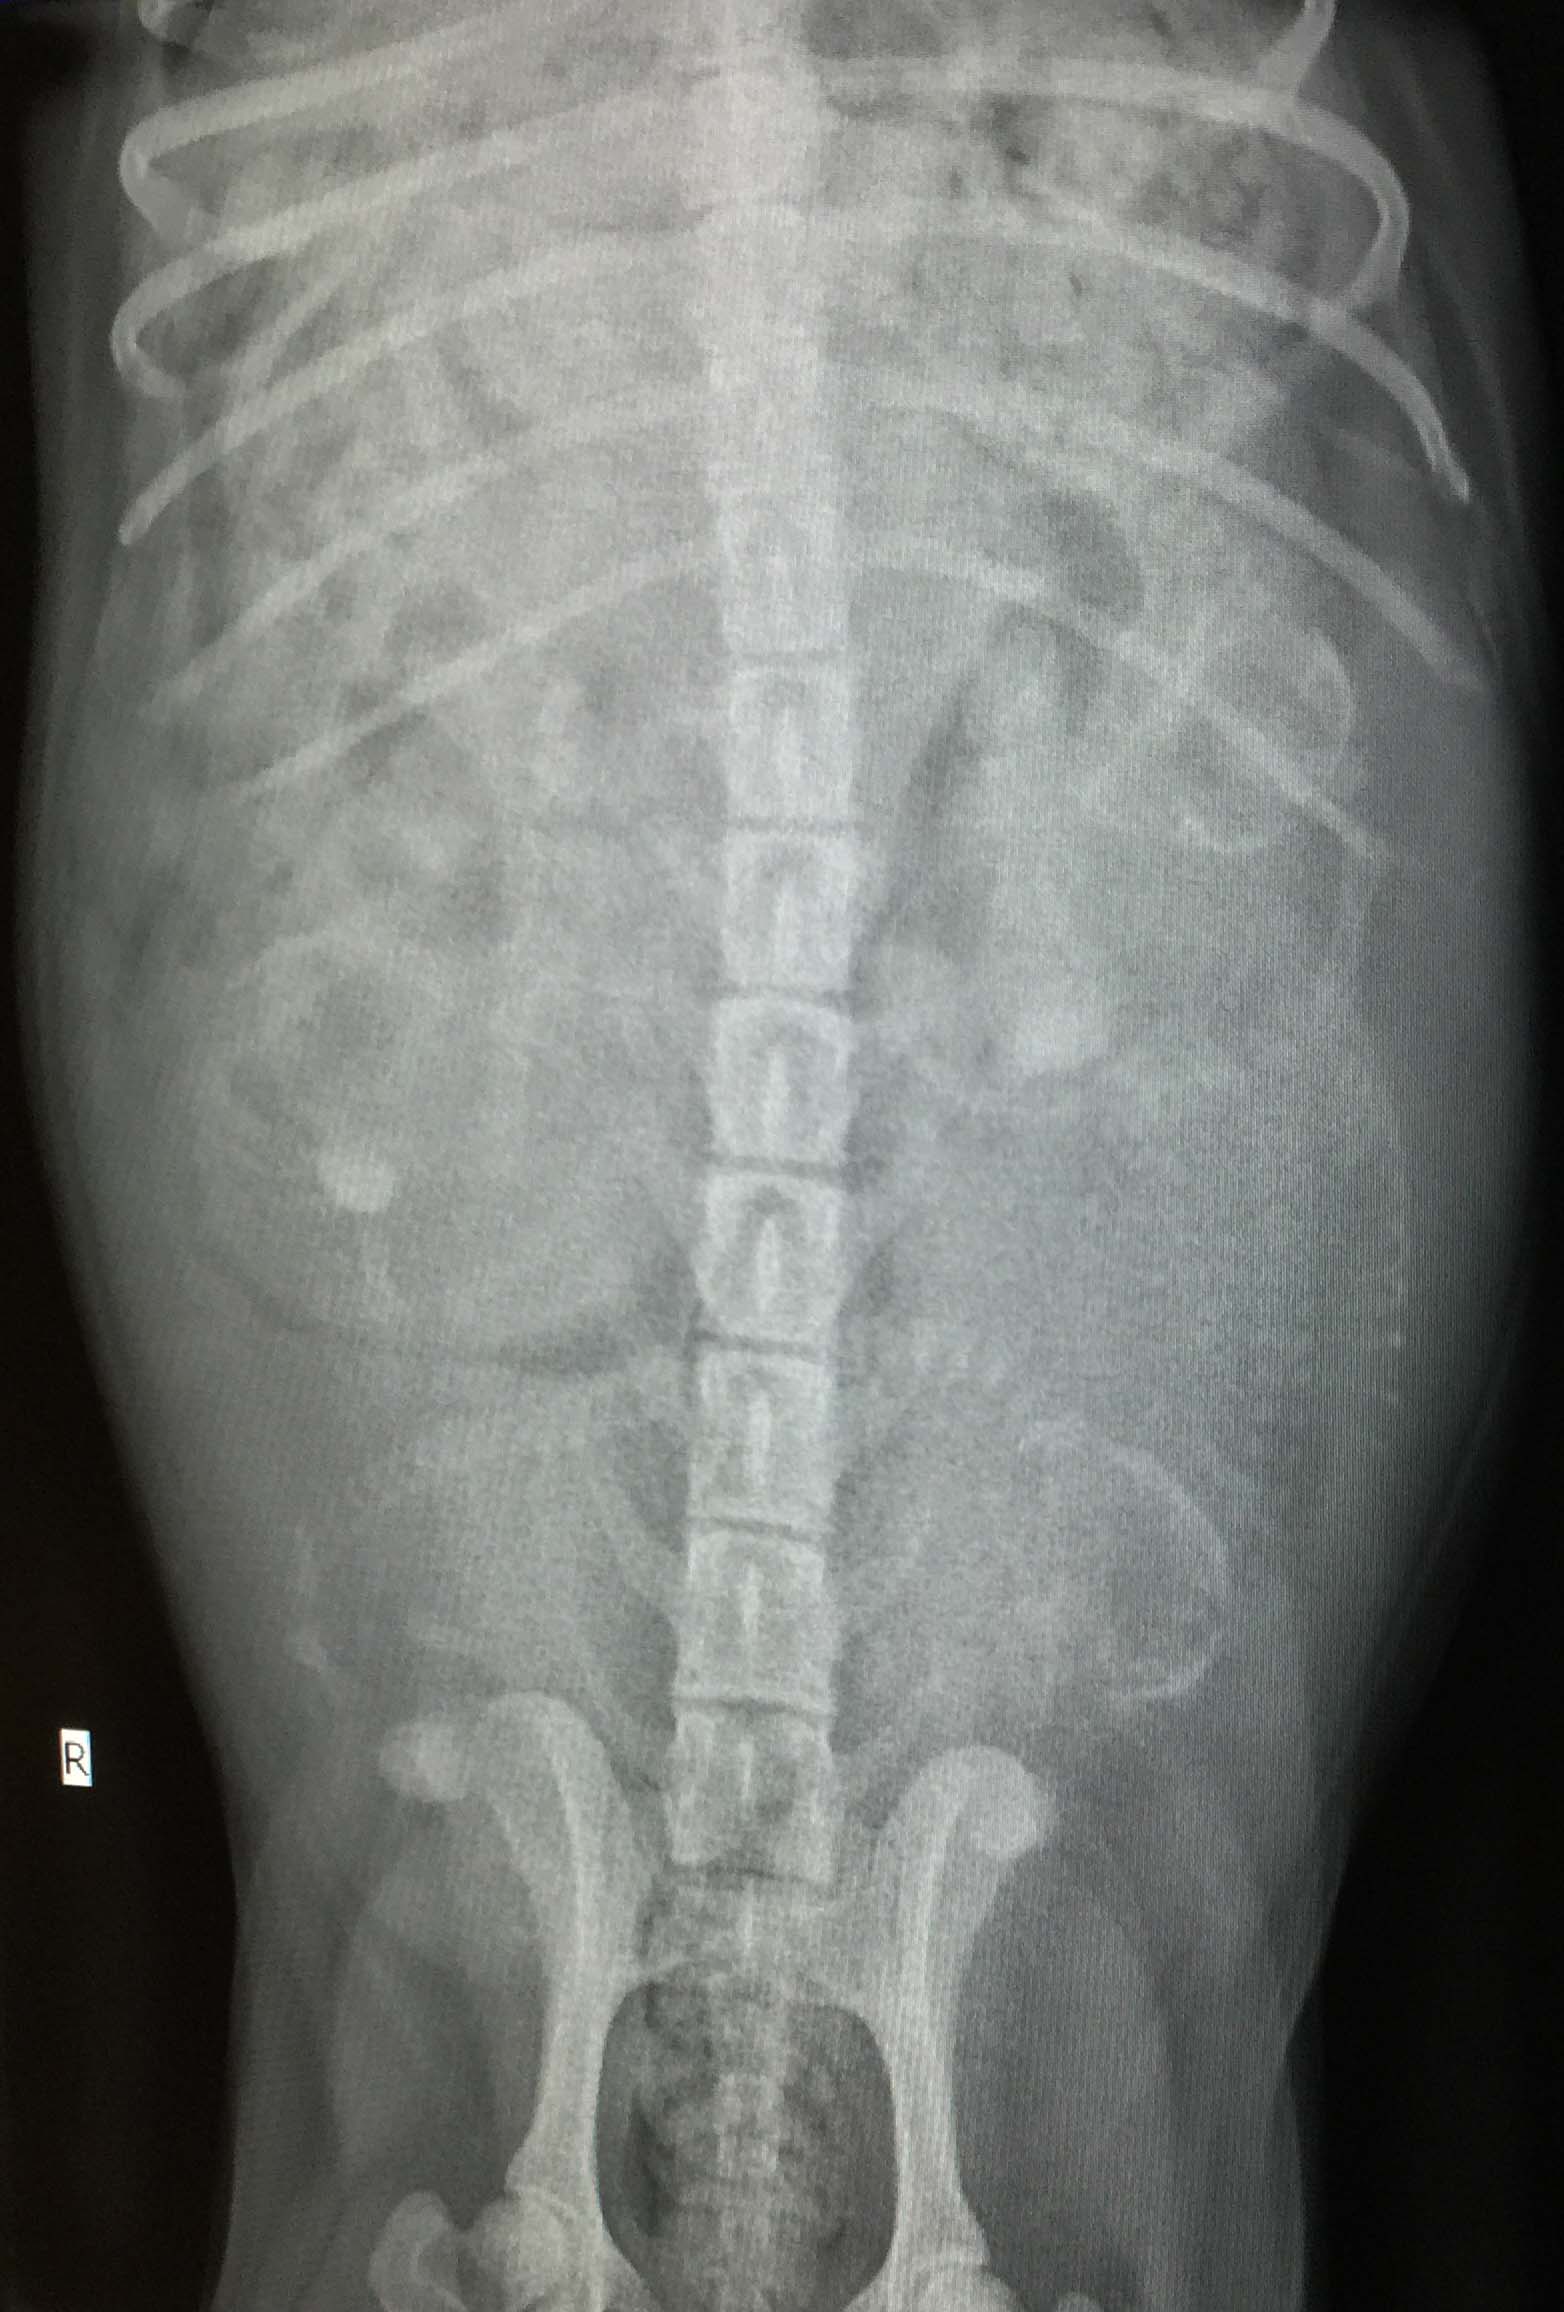

Heute war ein wichtiger Tag für Arusha. Allgemeiner Check und Röntgen von Arusha standen auf dem Programm. Nachdem in den letzten Tagen schon erste Bewegungen der Kleinen zu fühlen waren, waren wir natürlich super gespannt was wir heute auf dem Bild zu sehen bekommen. Auch die bereits 4,5 kg Gewichtszunahme sind beachtlich. Aber warum sollte Arusha ihr Geheimnis verfrüht preisgeben? Selbst die Aufnahme von heute lässt nur den Rückschluss zu, dass wir zwischen 4 und 6 kleine Traumpfoten erwarten.